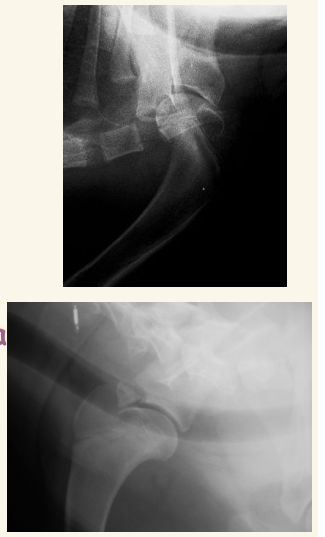

Escapula:

Hueso plano y protegido por musculos, fracturas son poco comunes. Si se dan suelen ser en la zona del cuello, longitudinales afectando a la espina o en la cavidad glenoidea. En cachorros mas comun por linea de crecimiento en el tuberculo de la escapula

Neoplasias (Condrosarcoma y a veces osteosarcoma) son mas comunes. Neoplasias: